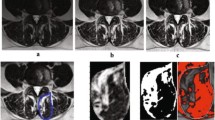

All measurements were performed by two orthopedic residents, who were trained in the MRI muscle assessment. The MRI images were measured through the two different image processing programs (ImageJ and Amira). The two observers measured the MRIs in a random order for both investigators. The CSA of the multifidus muscle (MF) and erector spinae muscle (ES) was measured at mid-disk level L4/5 and L5/S1 (Fig. 1), the CSA was single measured before applying any thresholds. FCSA and FCSA/CSA were determined using two different segmentation thresholds for differentiating muscle fibers and fatty muscle infiltration.

Circle method: Six regions of interest (ROIs) from the muscles of the MF and ES were taken from the visible areas of muscle tissue with least visual fatty infiltration. The maximum value that can be obtained from a sample ROI is regarded as the upper threshold to distinguish between muscle tissue and fat. Since the lower limit is usually 0 or close to 0, uniformly setting the lower limit at 0 is used to minimize errors (defined as Circle method) [14].

Overlap method: Outline CSA of paraspinal muscle (include ES and MF) and subcutaneous fat (SC) on both sides. By presenting the grayscale ranges for both CSA and SC as histograms and overlaying them, it was possible to identify signal intensities that were common to both images. The Overlapping area of the histograms represents the intensity of the fatty signal in the CSA (defined as Overlap method) [15].